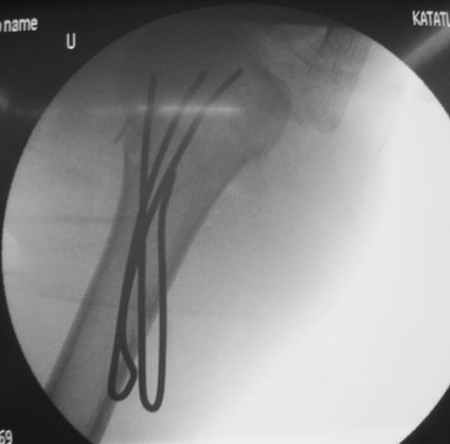

Спасибо за участие в дискуссии -перелом шейки плеча, для себя я прояснил многие технические моменты...

Посылаю послеоперационные Рг граммы.

Я и сам доволен результатом. В предпоследнем письме я кратко описал ход операции - закрыто репонировать не удалось( 2 недели с момента травмы и 1 неделя после неудачной репозиции) после удаления пучков спиц, пришлось сделать - 2см разрез на уровне перелома и с помощью периостального элеватора (золотое правило механики) *одеть* головку на дистальный отломок.

Спицы проводил через старые отверстия, вращая пучок импактором- направителем при его введении в головку.